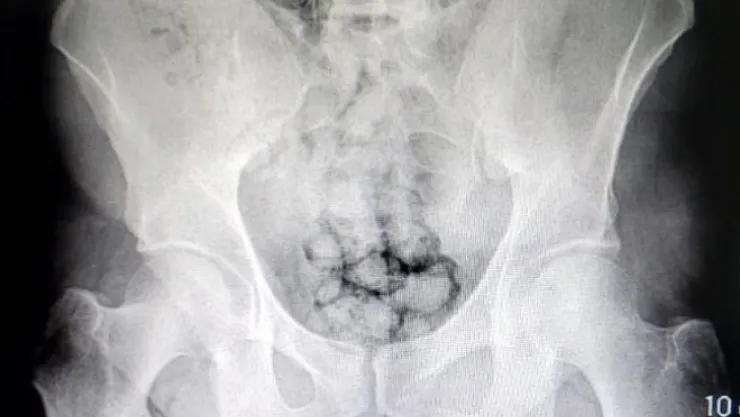

Kayseri İl Emniyet Müdürlüğü Narkotik Suçlarla Mücadele Şube Müdürlüğü ekipleri uyuşturucu madde ticareti yapan iki yabancı uyruklu şahsı takibe aldı. Ekipler, hareketlerinden ve mide bulantılarından şüphelendiği şahısları hastaneye götürdü. Burada röntgen çekinen şahısların midesinde farklı maddeler tespit edildi. Yapılan tıbbi müdahalede şahısların metamfetamin kapsüllerini yutarak midelerinde saklandığı belirlendi. Kayseri Valisi Gökmen Çiçek, operasyonla ilgili olarak, "Ne yaparlarsa yapsınlar Kayseri Emniyetinden kaçamayacaklar. İlimize uyuşturucu sokmak için denedikleri her yol emniyetimizin dikkati sayesinde başarısızlığa uğratılıyor. Bu sefer metamfetamin kapsüllerini midelerinde saklayarak ilimize sokmaya çalıştılar. Emniyetimizin dikkati sayesinde kıskıvrak yakalandılar. Gençlerimizi zehirlemelerine izin vermeyeceğiz. Tebrikler Kayseri Emniyet" ifadelerini kullandı.